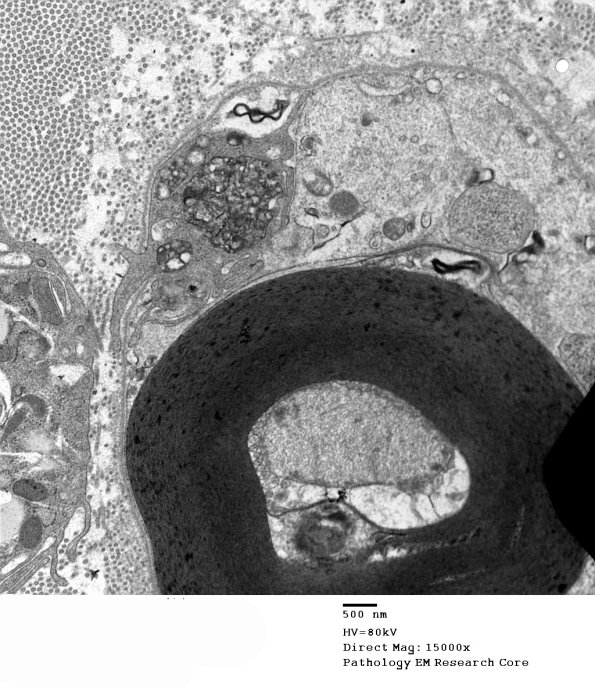

2F3A,B In these micrographs the process of macrophage-mediated demyelination has barely begun with a macrophage process originating outside the Schwann cell and basal lamina extending within the sheath contacting the otherwise normal myelin. Note the axon is intact. (electron micrograph)